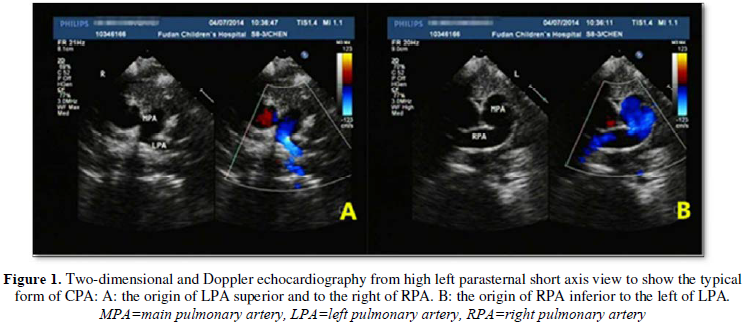

The direct sign of CPA was displayed at the

high left parasternal short-axis view and the suprasternal fossa view, while

the typical bifurcation disappeared in the routine left parasternal view. For

to the pulmonary artery and below the left pulmonary artery (Figure 1). For atypical form, in the high left

parasternal view, the main pulmonary artery continues to the right or left

pulmonary directly (Figure 2), then

the left pulmonary artery was located just above the right pulmonary artery or

the right pulmonary artery was located below the left pulmonary artery. There

were no other indirect echocardiographic signs of the single CPA.